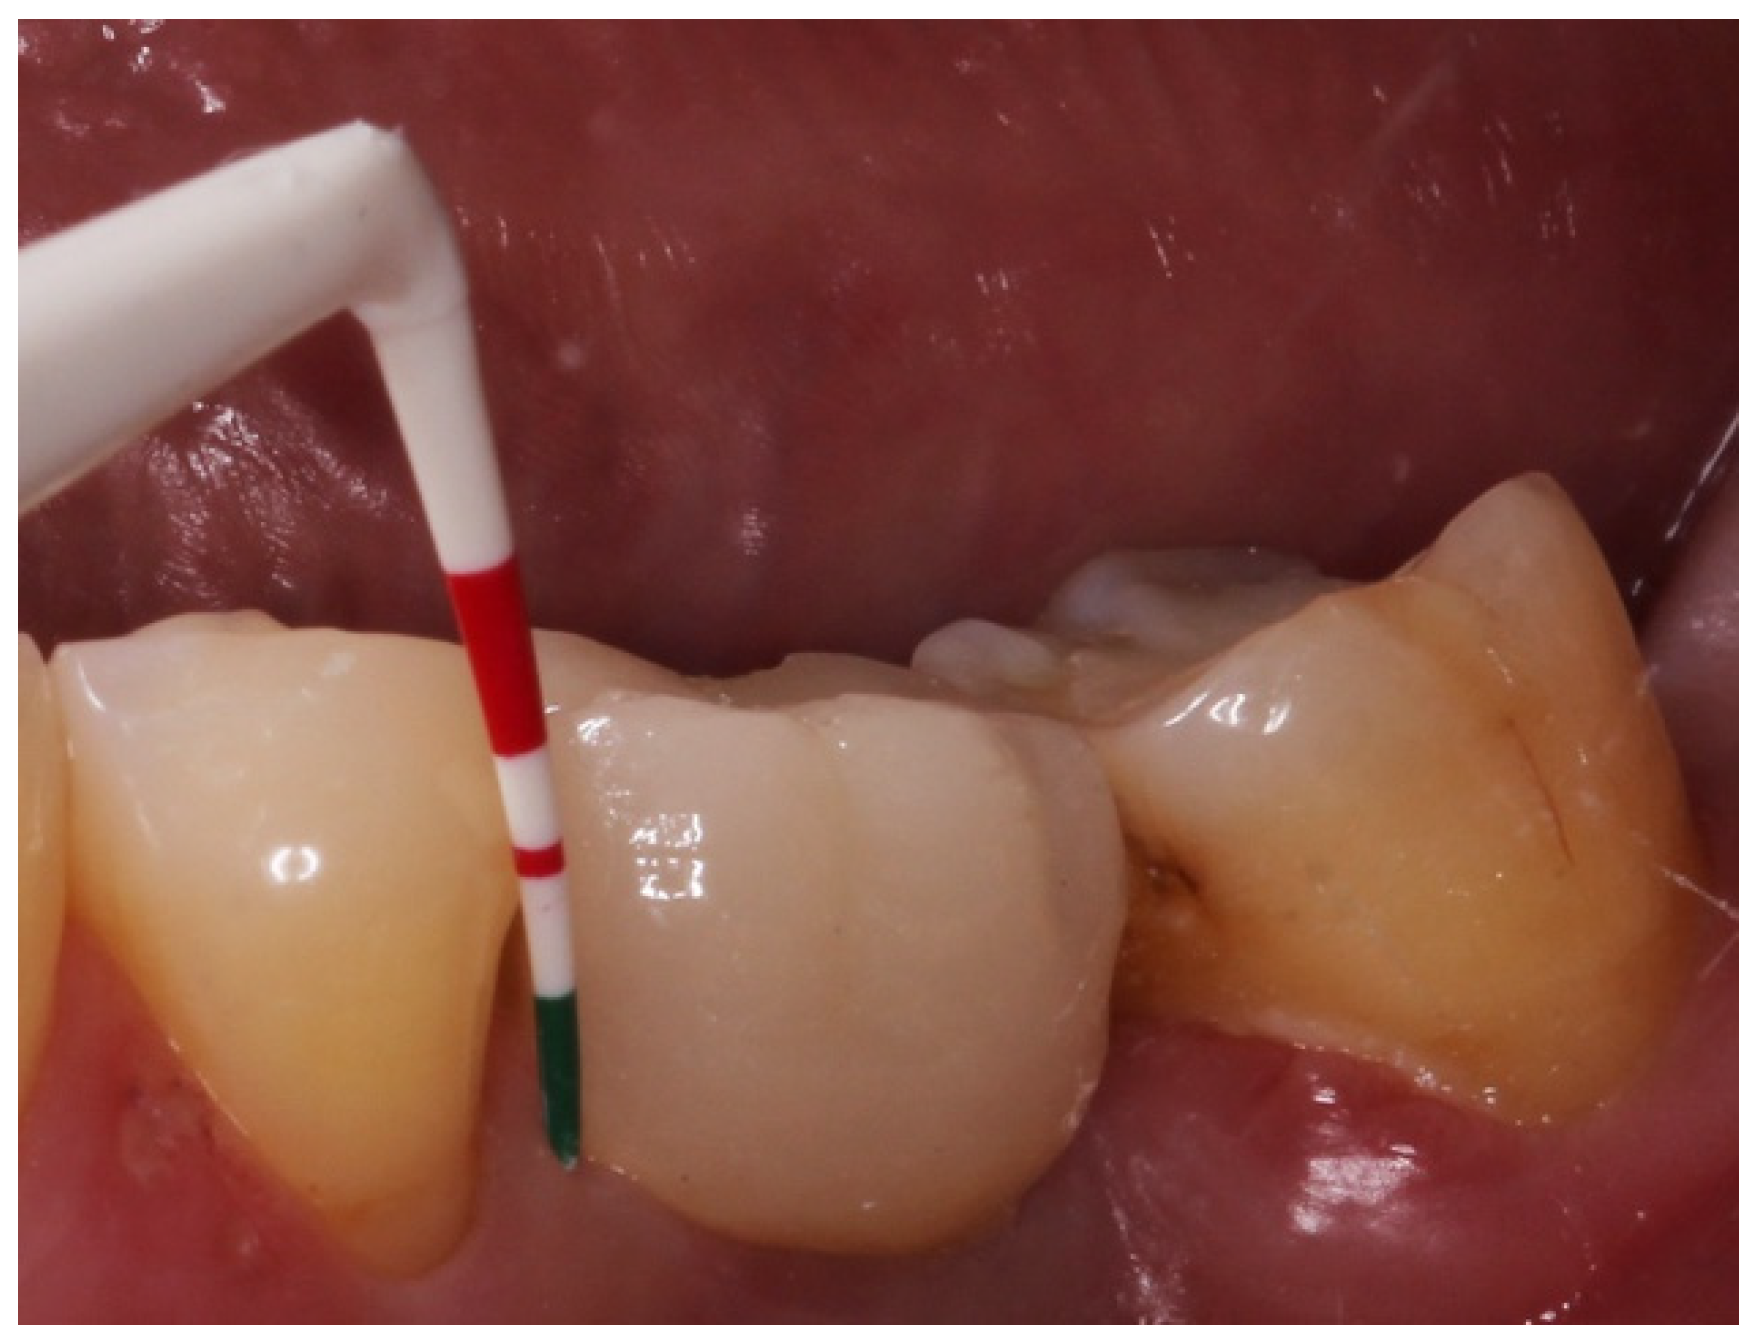

Variables related to the subject were collected; such as age, gender, tobacco consumption and history of periodontitis, as well as variables related to the implants. The main parameter was the presence of keratinized mucosa (KM), as well as the width of KM measured in millimeters in the mid-buccal surface of the implants with a periodontal probe CP 15 from Hu-friedy® (Frankfurt, Germany). The absence of KM was considered when there was non-keratinized mucosa at the gingival margin of the implant (Figure 1). Recession (the apical migration of the gingival margin) was measured in the mid-buccal surface from the cervical margin of the crown, where the gingival margin was located at the time of prosthesis placement. Other parameters were: Silness and Löe plaque index (Figure 2); probing depth using a plastic periodontal probe (Premier®) (at six points: mesiobuccal, buccal, distobuccal, mesiopalatal, palatal and distopalatal) (Figure 3); bleeding (its presence or absence was measured); suppuration (its presence or absence was measured); and bone level (distance, in mm, between the implant shoulder and the base of the defect) using Rhinoceros® software (Robert Mcneel & Associates, Seattle, WA, USA) on the parallelized radiographs. Bone loss due to peri-implantitis was considered when a crater-shaped image was observed surrounding the implant (taking as reference the most apical area of the crater) (Figure 4), accompanied by clinical signs such as bleeding or suppuration. The years since prosthesis placement were also noted. All data were collected by a single operator who visually analyzed the esthetics of the peri-implant tissues.

Figure 3.

Probing depth using a plastic periodontal probe.